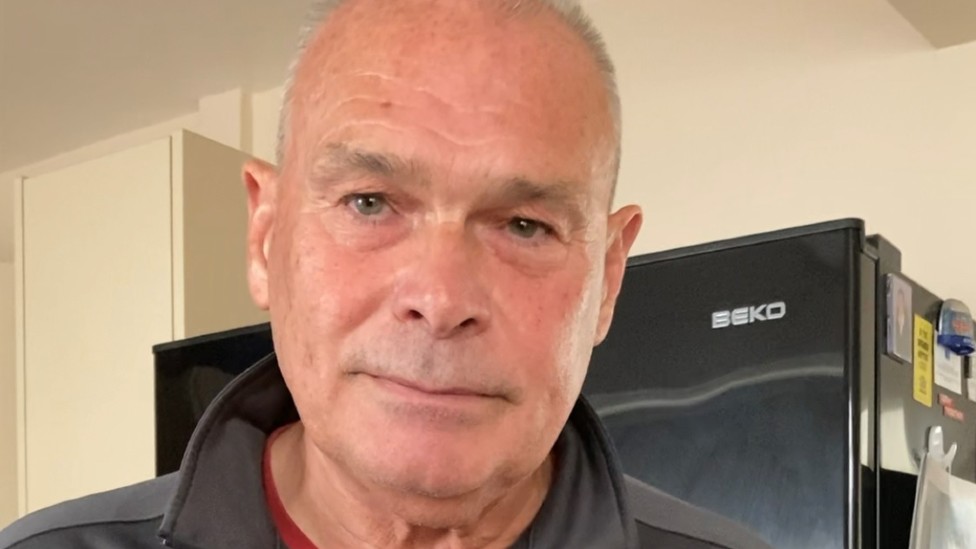

Muškarac koji je mislio da gubi sluh otkrio je da mu je zapravo deo čepića bio zaglavljen u uhu pet godina.

Volas Li, iz engleskog Dorseta, smatrao je da ima probleme sa sluhom zbog dugogodišnjeg rada u bučnoj avio-industriji ili da su možda posledica povrede koju je zadobio dok je igrao ragbi.

Odlučio je da poseti lekara nakon što je kupio aparat koji mu je pomogao da uoči mali beli predmet.

Li je rekao da je mu je laknulo kada mu je iz uva uklonjen predmet koji mu je pravio probleme.

Veteran Kraljevske mornarice veruje da se predmet zaglavio u uvu prilikom jednog putovanja avionom.

„Pre pet godina, kada sam bio u poseti porodici u Australiji, kupio sam ove čepiće za uši u koje možete da stavite nastavke, u zavisnosti od buke koju želite da ublažite“, rekao je on.

„Jedan od tih malih predmeta je od tada ostao unutra.“

Primetio je da mu se sluh pogoršava, kao i njegova žena, i počeo je da strahuje da će ogluveti.

Li je rekao da je beskrajno mnogo puta pokušavao da pročisti uši, ali bezuspešno, dodajući da je „ludeo“.

On je rekao da je hirurg za uho, nos i grlo (ORL) koji je uspešno uklonio blokadu bio „začuđen“.

„[Doktor] je u početku pokušao da ga istera tečnošću, ali pošto je bio zaglavljen godinama zbog nagomilanog tvrdog ušnog voska uopšte se nije pomerio“, ispričao je Li.

„Potom je probao minijaturnom pincetom koju je ubacio u ušni kanal… Zapravo sam mogao da osetim kako ga vuče, i odjednom je puklo.

„Odmah sam čuo sve u prostoriji. Magla koja mi je bila u glavi svih tih godina je nestala i čuo sam savršeno dobro.

„Bilo je to jednostavno olakšanje… kao da prvi put čuješ kako valja.“

Hirurg Nil De Zojsa u izjavi za BBC savetovao je ljude da ne pokušavaju da uklone predmete bez stručne medicinske pomoći jer bi to moglo da uzrokuje infekcije ili druge probleme.